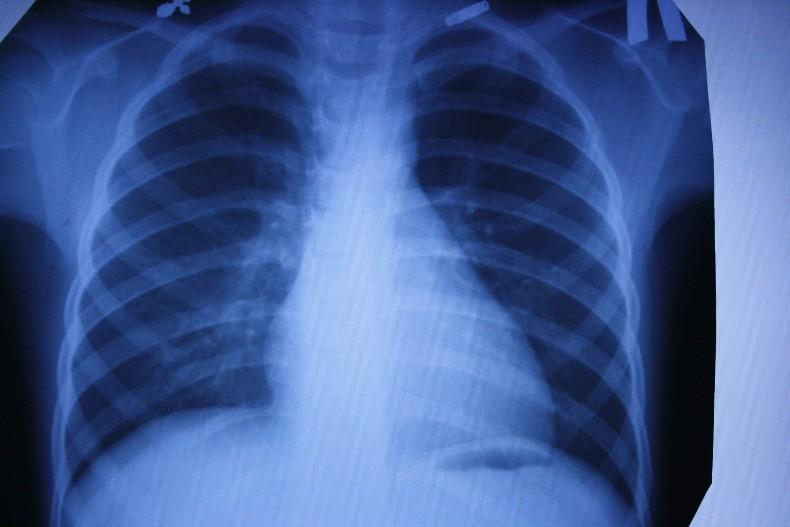

Рентген

Наиболее старый и привычный метод визуализации человеческого тела. Применяют рентген повсеместно, от хирургии до стоматологии. Метод прост и понятен: человека облучают особыми лучами, которые легко проходят сквозь мягкие ткани и задерживаются в твёрдых. Благодаря этому принципу, на фотоплёнку или датчик, расположенные на противоположной от источника лучей стороне, передаётся изображение, а в распоряжение врача попадает рентгенография или рентгеноскопия.

Главные плюсы такого обследования: быстрота и стоимость. Рентгеновскими аппаратами оснащены практически все больницы, процедура проходит быстро и стоит недорого.

Главные минусы: облучение и качество изображения. При проведении рентгенографии пациент облучается, а картинка получается двумерной. Врач с трудом может разглядеть внутренние органы по отдельности, поскольку их тени перекрывают друг друга. Также невозможно детально разглядеть хрящевую ткань и мозг. Хрящи практически не задерживает лучи, мозг надёжно закрыт черепной коробкой. Для их исследования рентгенография не подойдёт.

Наиболее эффективно будет проводить рентгенографию при повреждениях костей, суставов и зубов.

Флюорография

Ещё один тип обследования, которому регулярно все жители нашей страны. Флюорографию “изобрели” почти сто лет назад. Это своего рода ускоренная рентгенография. Учёные предложили фотографировать экран с изображением, полученным при рентгенографии. Это позволило сделать процедуру более быстрой и массовой. Скрининг-тесты начали делать всем, чтобы выявлять скрыто протекающий туберкулёз лёгких.

Главный плюс процедуры — быстрота, главный минус — качество изображения. Пациент также получает дозу облучения, а врач довольно размытую картинку, поэтому флюорографию рекомендуется дополнять анкетированием и лабораторными тестами на наличие туберкулёза.